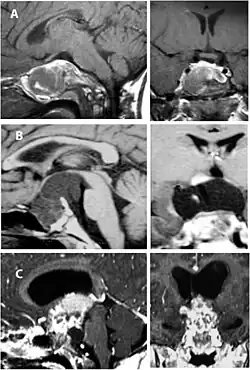

Imaging scans for craniopharyngioma

A physician can conduct a few scans and tests to diagnose a person with craniopharyngioma.[19] High-resolution magnetic resonance imaging (MRI) is commonly used as a diagnostic tool; however, computer tomography (CT) remains the gold standard imaging choice for craniopharyngioma diagnosis as it can detect the severity of the calcification within the tumour.[20]

In some cases, a powerful 3T (Tesla) MRI scanner can help define the location of critical brain structures affected by the tumor. The histologic pattern consists of nesting of squamous epithelium bordered by radially arranged cells. It is frequently accompanied by calcium deposition and may have a microscopic papillary architecture. A computed tomography (CT) scan is also a good diagnostic tool, as it detects calcification in the tumor.[21]

-

CT scan showing a craniopharyngioma -

Enhanced T1 weighted MRIs of craniopharyngiomas -